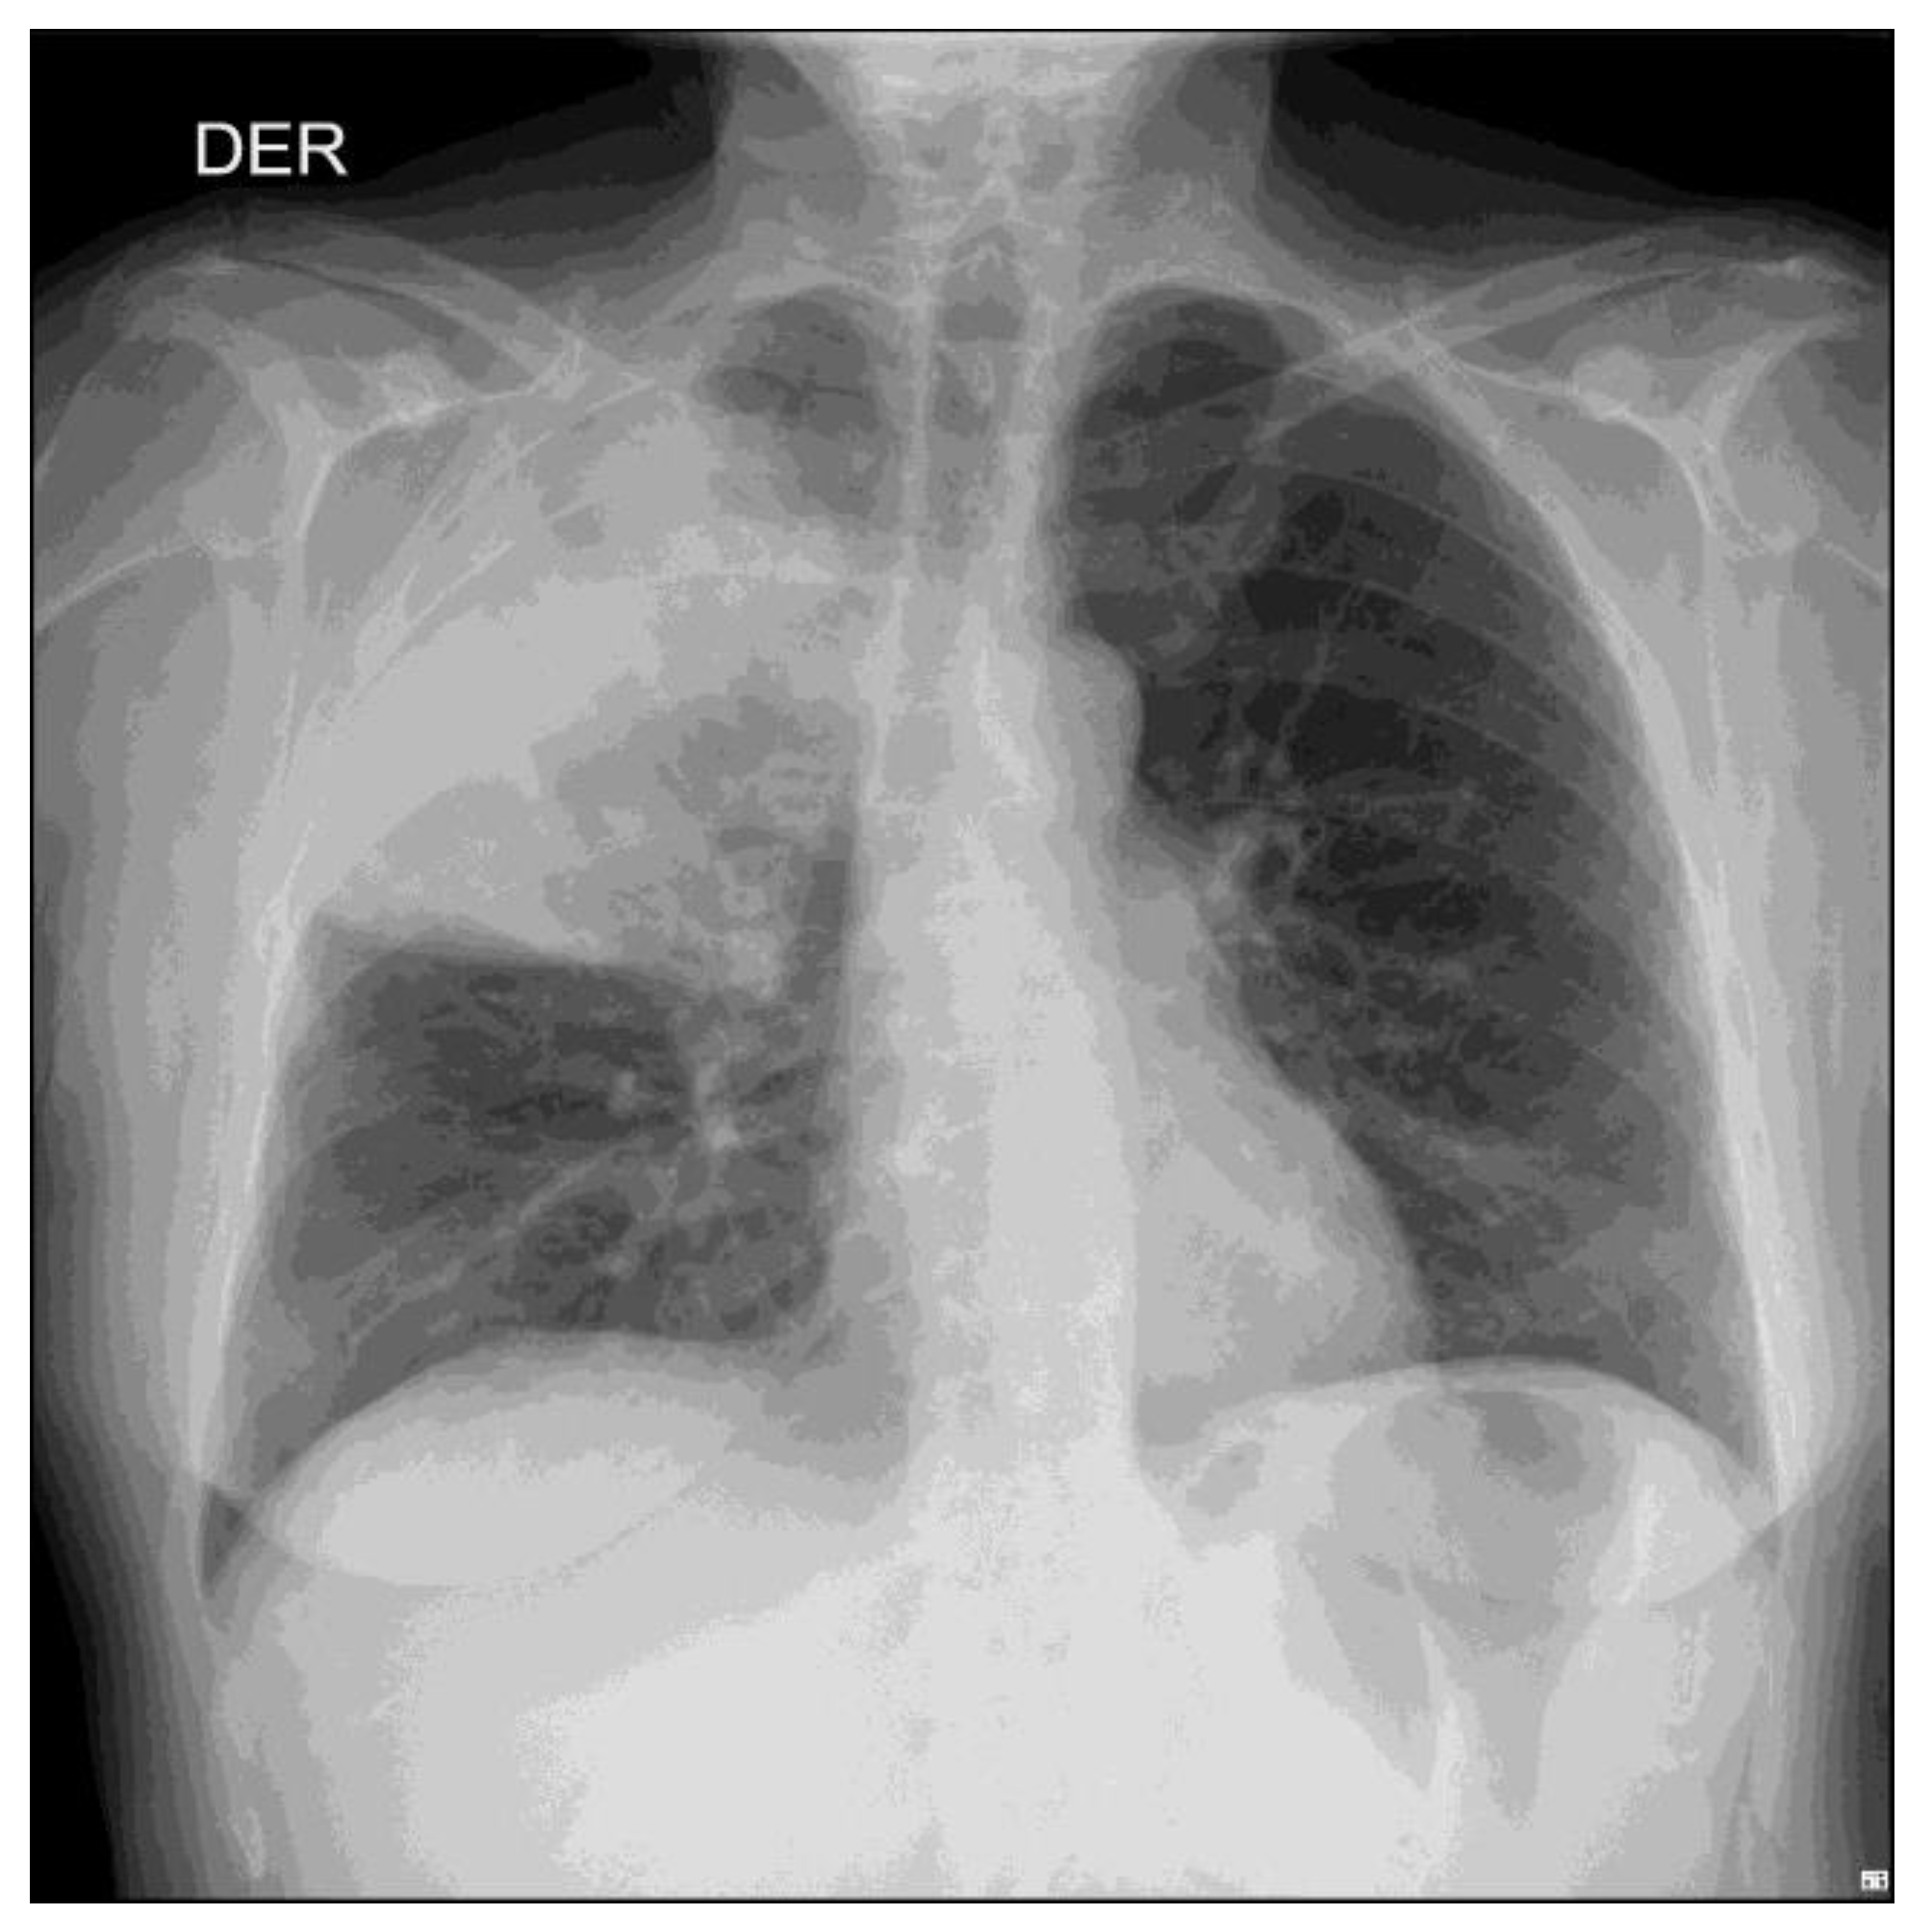

A 57-year-old woman, previously healthy, presented with a 7-day history of cough with brown sputum, sudden onset of chills, subjective fever, malaise and pleuritic pain in the right hemithorax. At admission, the patient was in poor general condition with tachycardia, fever, and tachypnea. Respiratory examination revealed bronchophony in the upper third of the right hemithorax. The initial investigations showed a high C-reactive protein (27.2 mg/dL), leukocytosis (26,700/mm3), neutrophilia (25,200/mm3) and a chest X-ray with a radiopaque image in the right upper lobe (Figure 1). A diagnosis of community-acquired pneumonia was considered, and intravenous antibiotic therapy was started with i.v. clarithromycin 500 mg BID and i.v. ampicillin- sulbactam 3 g QID.

Figure 1.

Chest radiograph with right apical radiopacity.